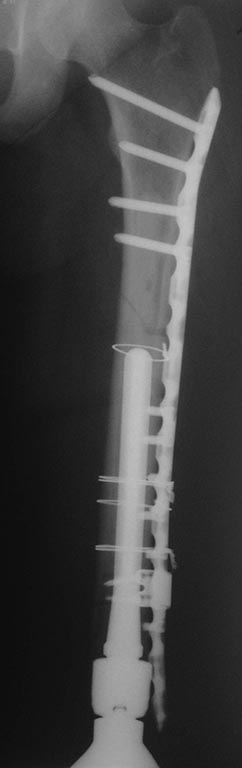

[Ortho] перипротезный перелом в области колена

дискуссии похоже не получилось, выкладываю постоп снимки.